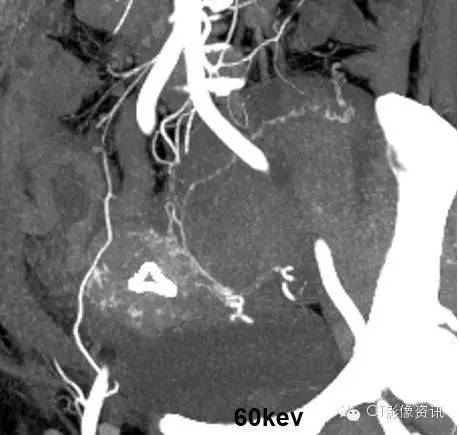

4、能谱单能量分析

单能量低keV,可以使原来难以结构清晰显示,为临床提供更多的病变信息。